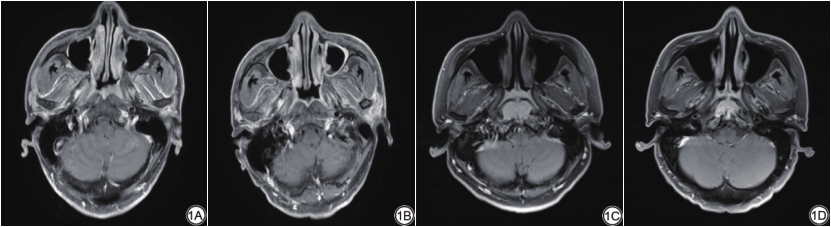

两位具有10年诊断经验的放射科医生(主治医师、主任医师)根据实体肿瘤标准(response evaluation criteria in solid tumors,RECIST 1.1[22])对CCRT后的MRI图像进行治疗反应评估,分为完全缓解(complete response,CR)、部分缓解(partial response,PR)、疾病进展(progressive disease,PD)、疾病稳定(stable disease,SD)。我们定义CR为完全反应组,PR、SD、PD为非完全反应组。意见不一致时,协商达成一致结果。图1为鼻咽癌治疗前后MRI图像。